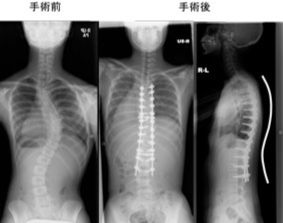

また、頚椎症性脊髄症や側弯症などの疾患に対しては、最新の設備を駆使して手術を行っています。具体的には、CTナビゲーションや脊髄刺激モニタリング、自己回収輸血などを利用して、安全性に配慮した手術を実施しています。また、新しいインプラントの導入により、人間の本来の弯曲に近い矯正術が可能となっています。